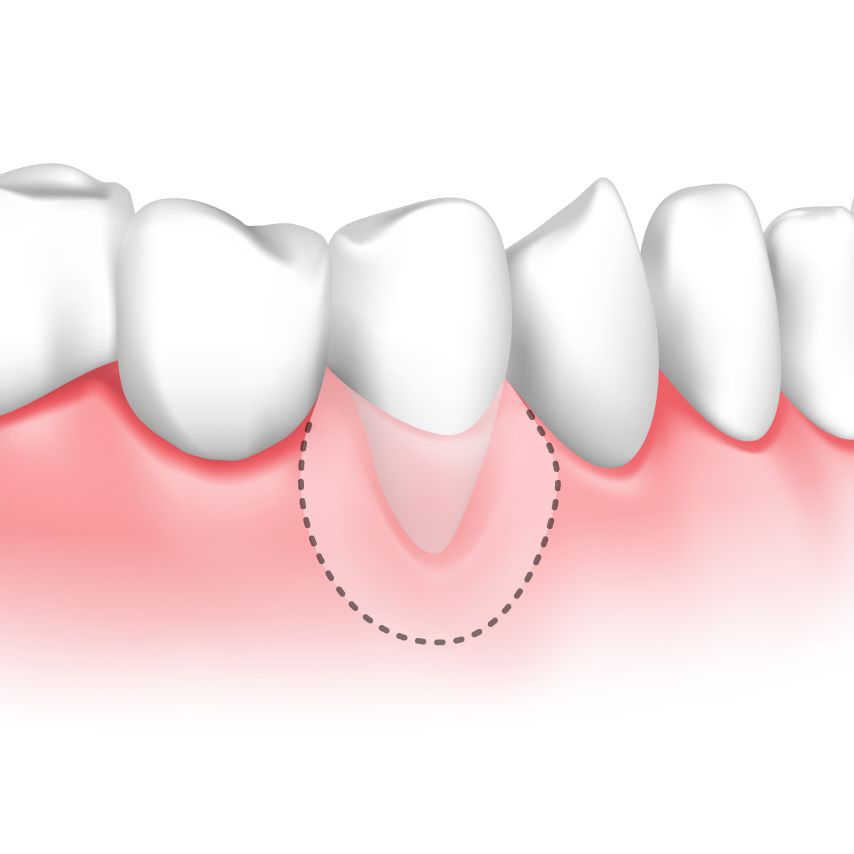

Soft-tissue Grafting

Gum grafting involves transplanting gum tissue to repair a damaged gum line. The procedure can use your own gum tissue from another area of your mouth, donor tissue, or synthetic tissue The tissue is then transplanted to cover your tooth roots, even your gum line, and minimize further recession.